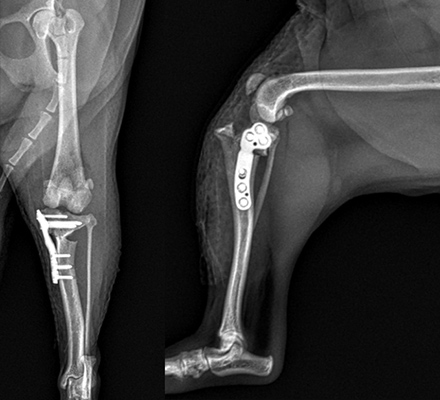

골절

절단을 피하고 다리를 살리는 치료

많은 병원에서 절단이 불가피하다고 판단한 환자들이, 예은동물의료센터에서 수술 후 성공적으로 회복되었습니다.

- 응급 골절 수술부터 타병원 수술 후 재수술까지 치료 가능

- 최신 재생치료(줄기세포, 항생제 칼슘비드, 겐타콜 등)를 활용하여 다리 재건 가능

- 단순한 골절 치료가 아닌, 환자의 전체적인 상태를 고려한 맞춤형 치료 제공

골절수술

- 요척골 단순골절

- 4살, 이탈리안그레이하운드

고난이도 상완골 원위부 골절

- IOHC, 상완골과골절

- 4개월 시추 2.6kg

고난이도 소형견 골절 수술